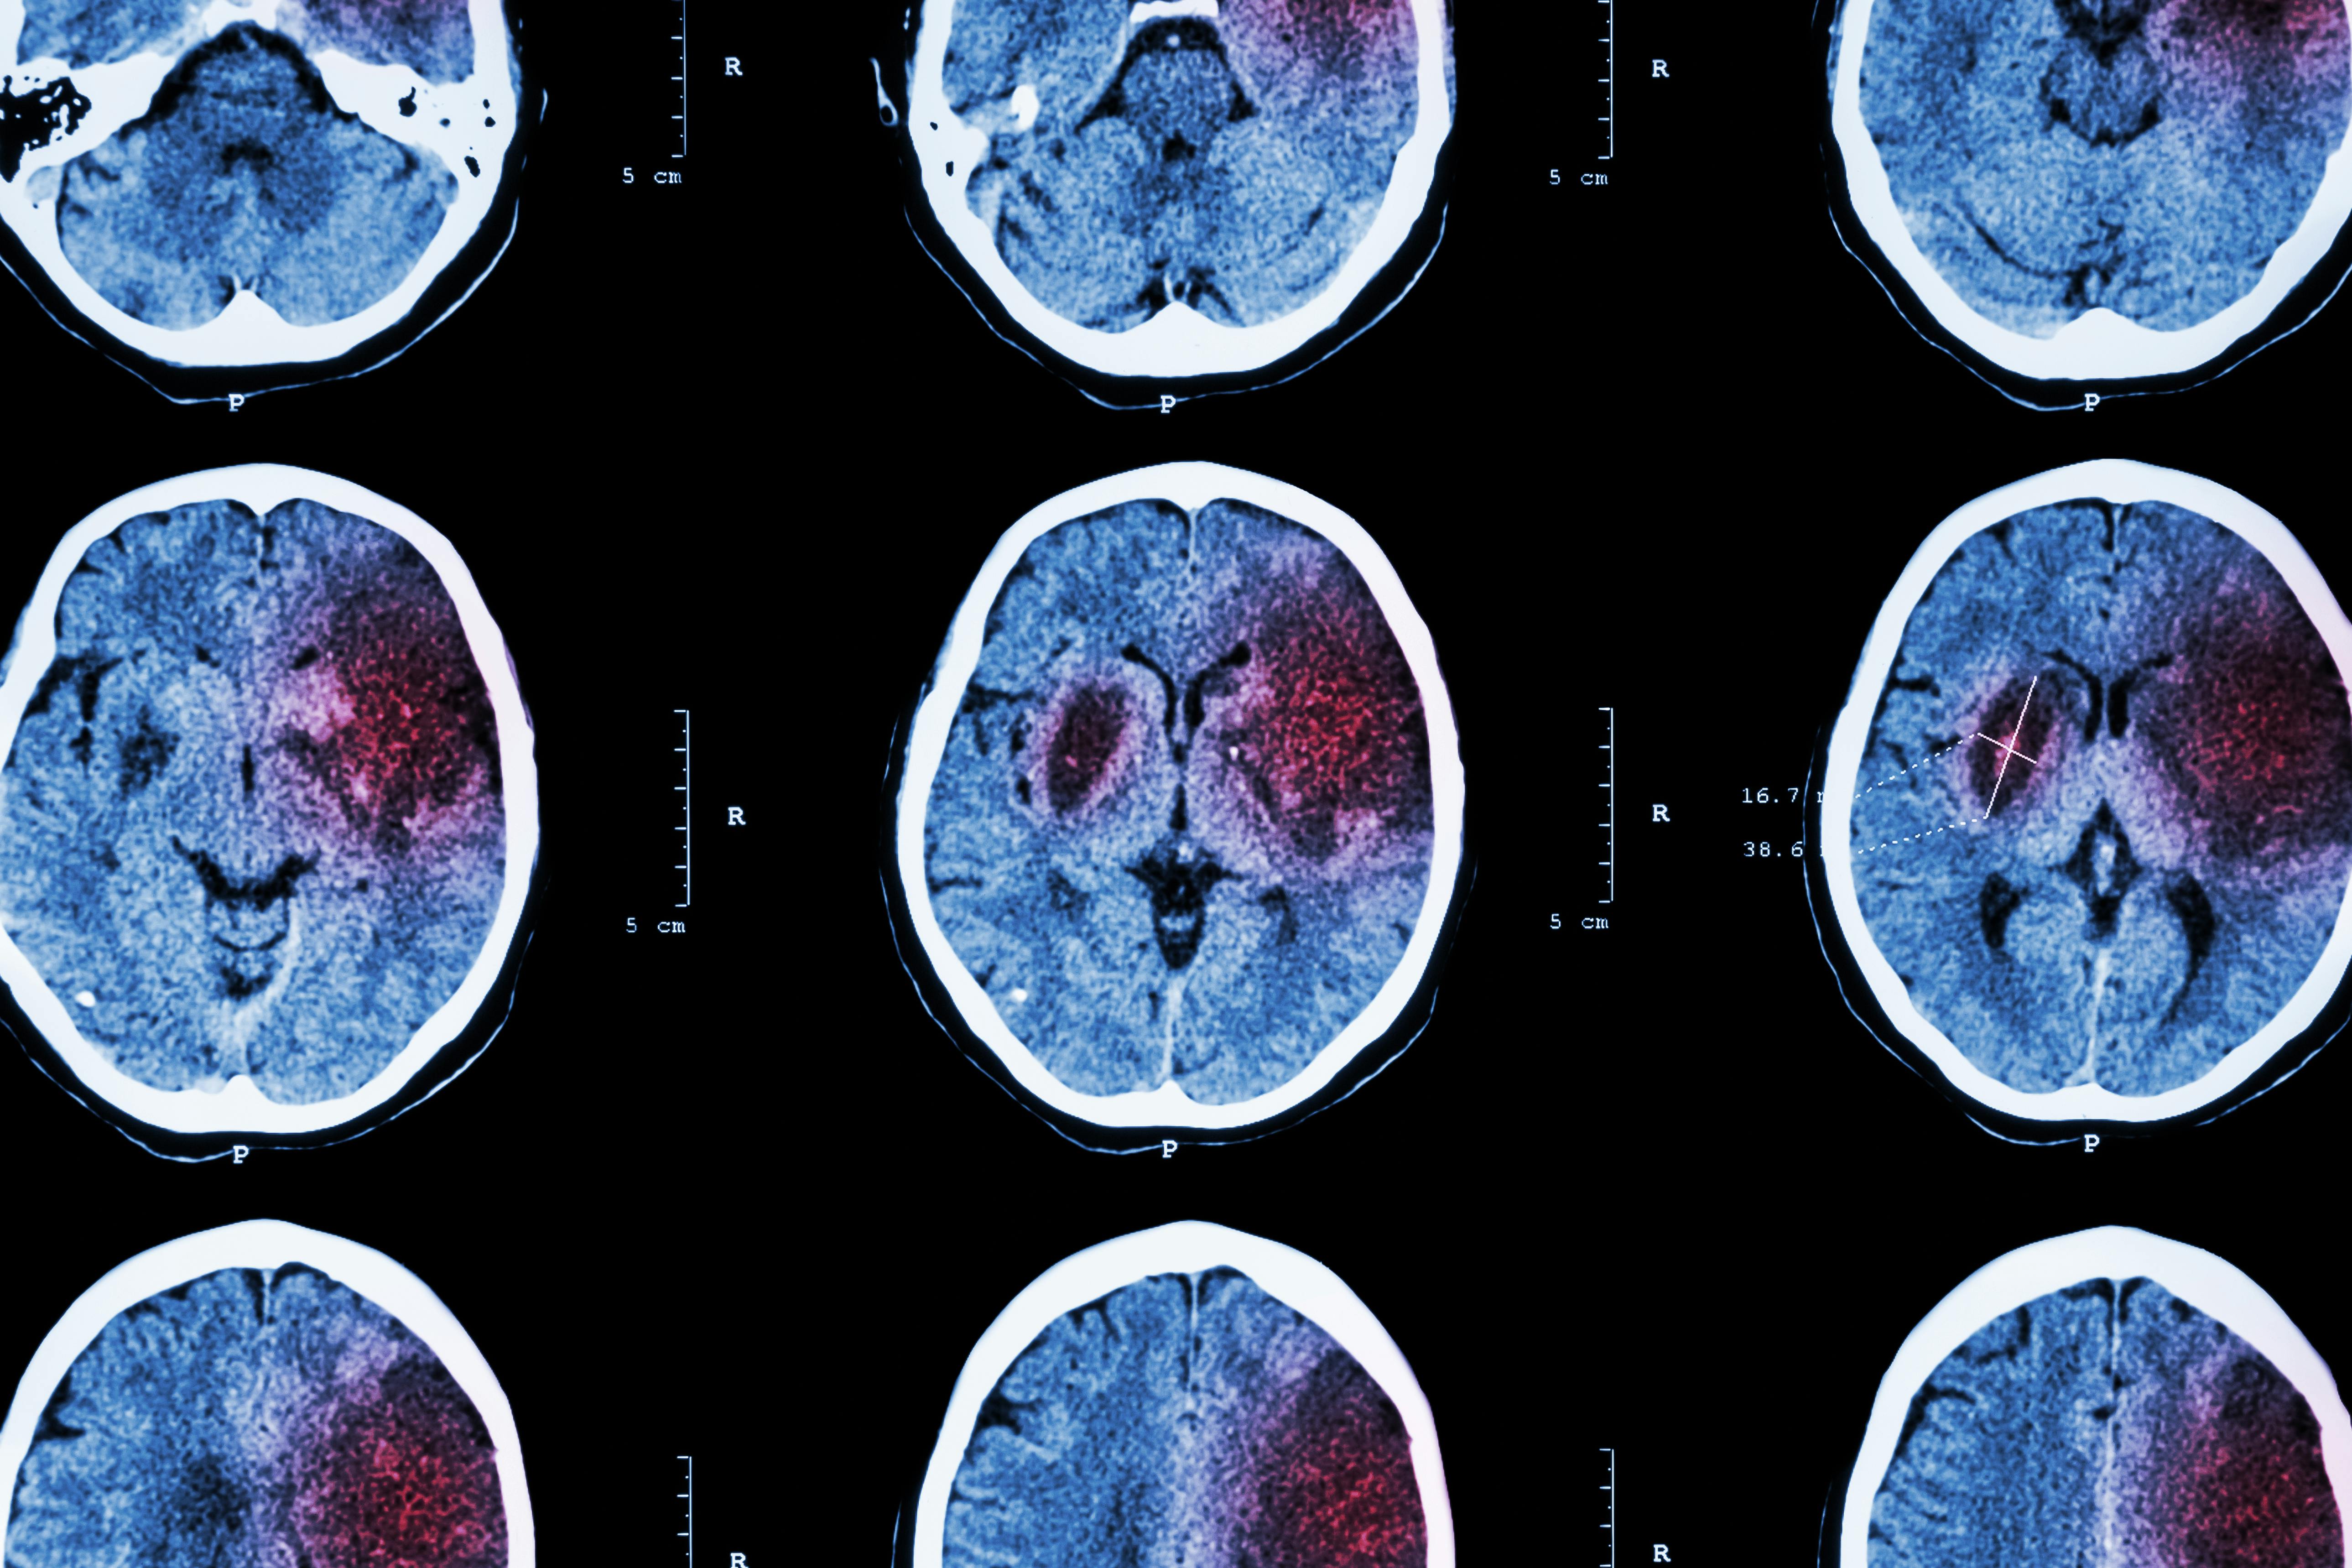

About a third of ischemic stroke survivors are eligible for endovascular thrombectomy, but more than 40% of people who receive endovascular therapy are “initially seen at hospitals that don’t offer the treatment,” necessitating a transfer. The vast majority of stroke patients face “prolonged time to transfer – a process known as door-in-door-out – which reduces their chance of receiving endovascular therapy and increases their chances of leaving the hospital with significant disability.”

A study published in The Lancet Neurology focused on over 20,000 patients with acute ischemic stroke, and found that “just 26% of transfers occurred within 90 minutes, the maximum time recommended by the American Heart Association. The likelihood of a patient receiving endovascular therapy declined steeply as transfer time delays grew. Patients with transfer times between 91 minutes and three hours had 29% less chance of receiving a thrombectomy.” Stroke patients with longer door-in-door-out times had “more complications after treatment and a lower likelihood of being able to walk independently after leaving the hospital.”